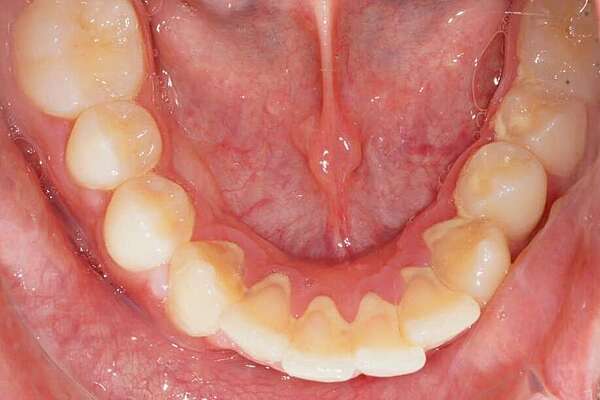

Important encombrement traité par gouttières